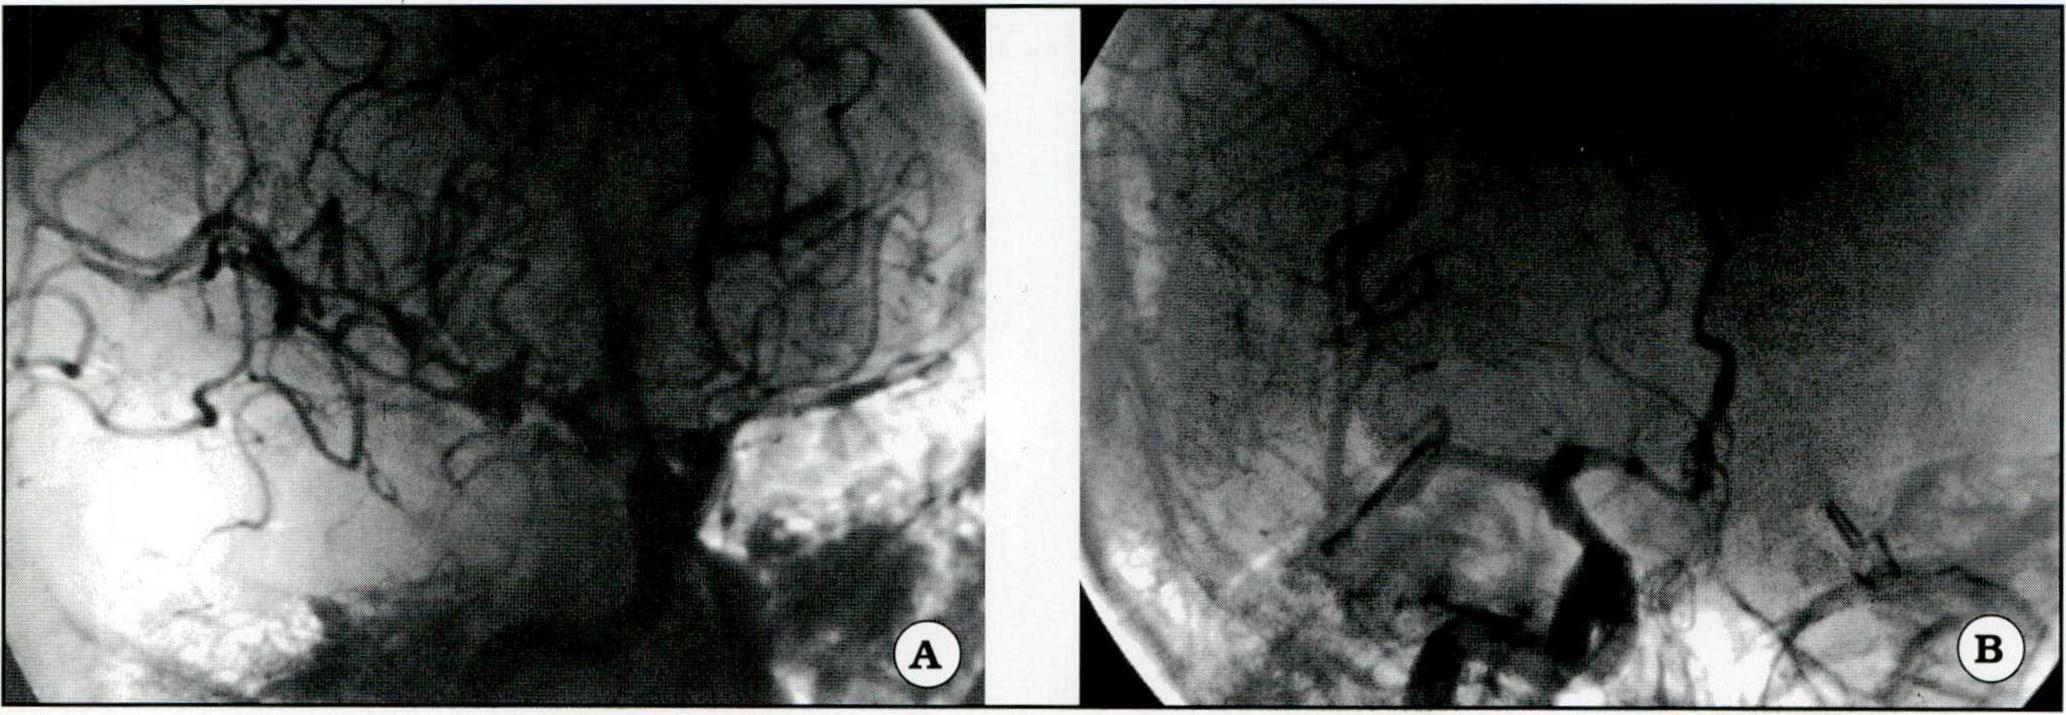

- Aneurismas múltiples: silviano derecho y aneurisma carotídeo contralateral ya clipado (Fig. 3).

Fig. 3. A. Aneurismas múltiples. Se observa el aneurisma silviano derecho y un clip aplicado a un aneurisma carotídeo izquierdo. B. Clipado del aneurisma silviano.